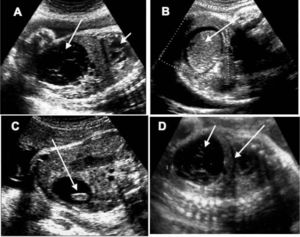

Se trata de tumoraciones quísticas de carácter funcional y naturaleza benigna, cuya etiología no está aún perfectamente aclarada. El diagnóstico ecográfico es relativamente fácil, ya que se presentan como formaciones anecoicas, uniloculares redondeadas de paredes finas y regulares que asientan al lado de la vejiga. En ocasiones, presentan un contenido intracavitario con niveles (quistes hemorrágicos) y estructura interna multilocular (tabiques) (fig. 1). No son infrecuentes los fenómenos de torsión y de necrosis dentro de la cavidad que distorsionan la regularidad de su contenido, presentando formaciones solidoquísticas que hay que diferenciar de los más infrecuentes teratomas ováricos fetales

Quistes ováricos fetales. A) Corte sagital de un feto de 32 semanas de gestación. La flecha corta señala la silueta cardíaca; la flecha larga delimita una tumoración quística ovárica con límites bien delimitados y seudotabiques en su interior. B) Quiste de ovario de un feto hembra de 30 semanas de gestación. La flecha señala su contenido hemorrágico. C) Quiste ovárico de un feto de 34 semanas con contenido sólido (flecha). D) Debajo del diafragma (flecha larga) se dibuja una tumoración ovárica fetal eminentemente quística (flecha corta) con contenido semisólido en su interior, que se hace más evidente en las zonas más declives.